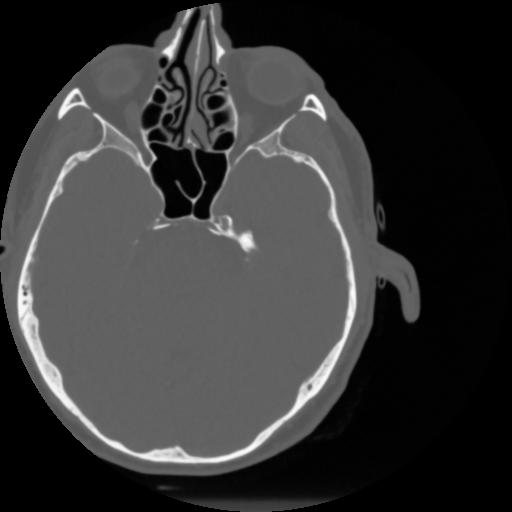

4 CEREBRO,,Vol,0.5,CEREBRO,,